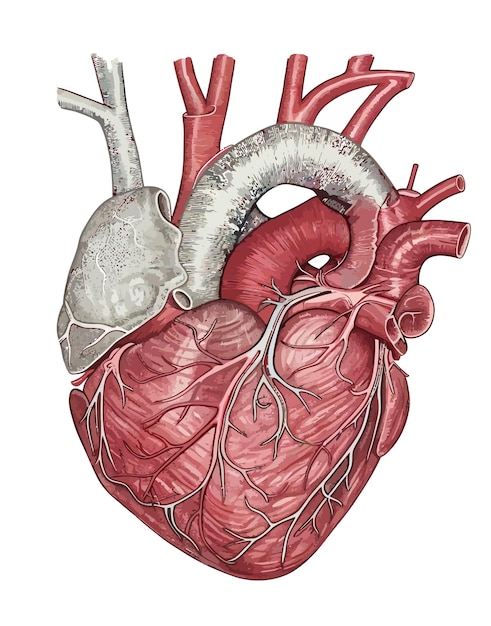

Раздел: Фотопанорама